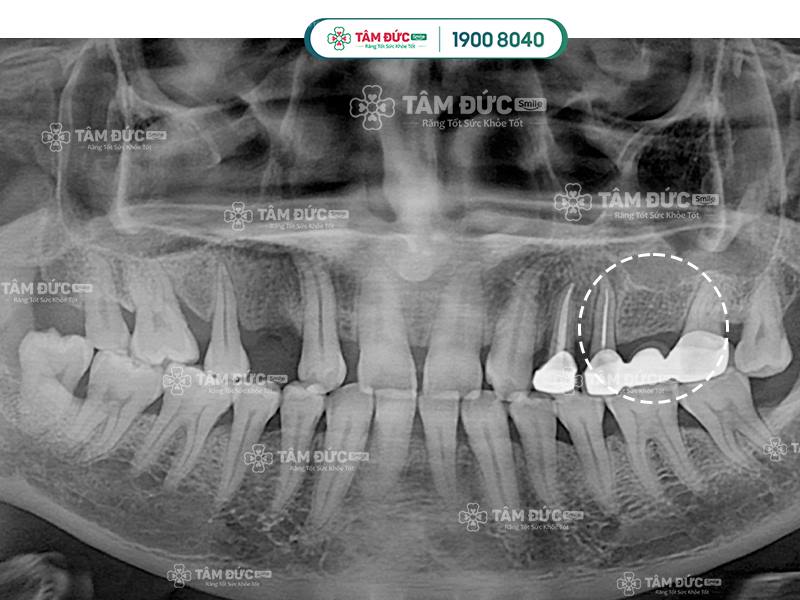

Cầu răng sứ không thể ngăn chặn tình trạng tiêu xương hàm khi mất răng